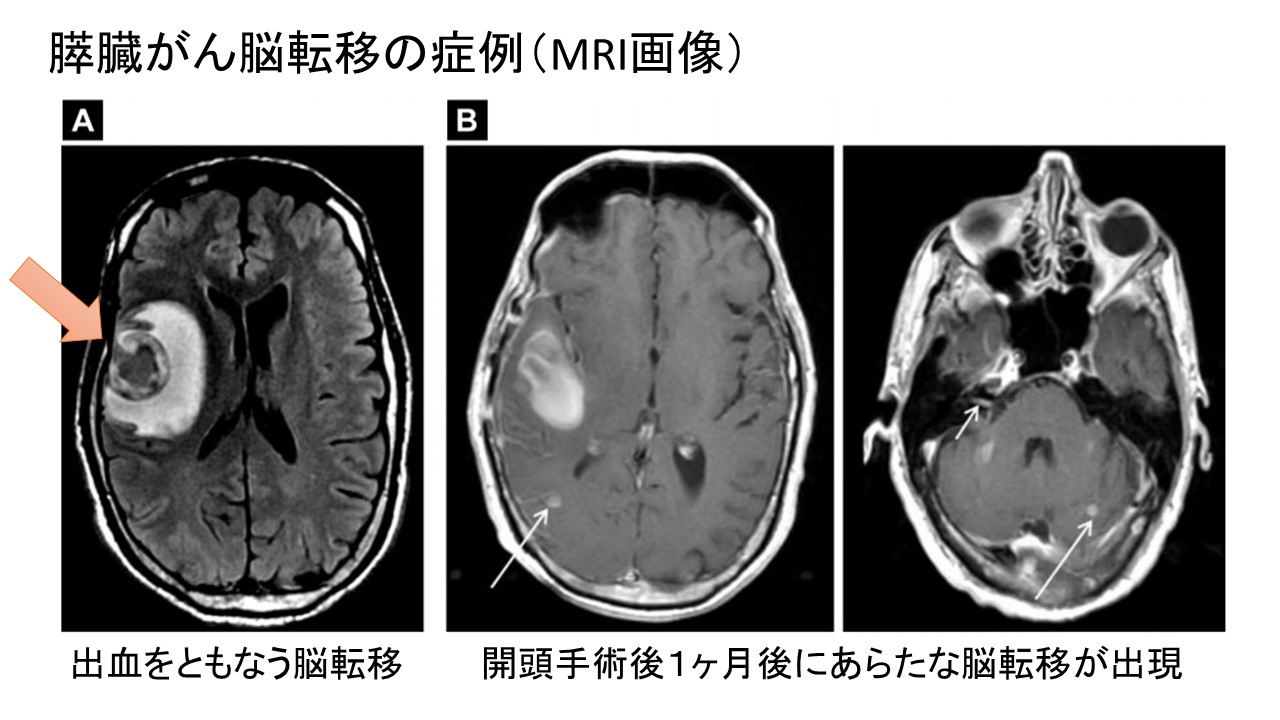

膵臓がんの脳転移 症状 診断 治療 余命および特徴的な遺伝子異常と